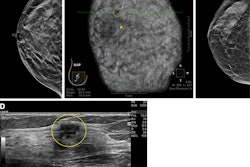

Images depict a 43-year-old woman with a malignant nonmass lesion that was diagnosed as microinvasive ductal carcinoma. (A) Transverse and (B) longitudinal ultrasound images show a hypoechoic nonmass lesion (solid arrows) with segmental distribution in the left breast. The lesion has associated calcifications (dashed arrows in A). (C) Longitudinal color Doppler ultrasound image shows high vascularity. (D) Magnified image in the mediolateral oblique view from screening mammography shows grouped calcifications (arrows), which are considered a mammographic correlate of the ultrasound-detected nonmass lesion (A radiopaque marker attached to the skin is visible in the image because the mammographic exam was performed after screening breast ultrasound). Ultrasound-guided core needle biopsy and pathologic examination revealed ductal carcinoma in situ, but the lesion was upgraded to microinvasive ductal carcinoma at subsequent surgery (2.5-cm ductal carcinoma in situ, histologic grade II, estrogen receptor-positive, progesterone receptor-positive, human epidermal growth factor receptor type 2-negative).RSNA